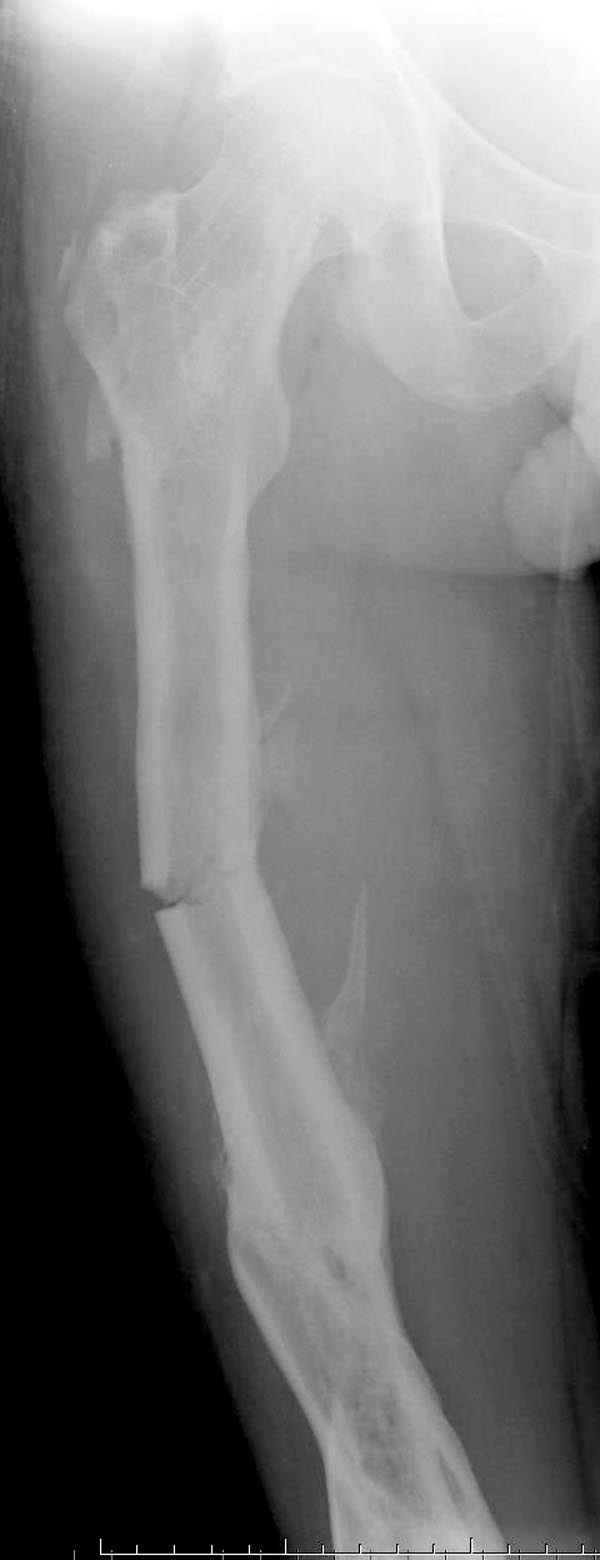

Мы не дождались “Happy End”, у больного IQ в пределах 70%, через 6 месяцев вернулся после небольшой травмы, споткнувшись получил перелом

того же бедра (рис №7).

При обзоре причин перелома, на снимке №2 обнаружили, что один из стержней аппарата наружной фиксации проходил только через передний кортекальный слой, что создало стрессовую зону на бедре и в результате перелом из-за незначительной травмы.